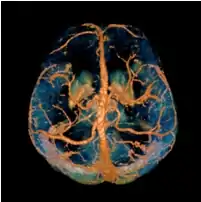

Quantitative susceptibility mapping (QSM) provides a novel contrast mechanism in magnetic resonance imaging (MRI) different from traditional susceptibility weighted imaging.[1][2][3][4][5] The voxel intensity in QSM is linearly proportional to the underlying tissue apparent magnetic susceptibility, which is useful for chemical identification and quantification of specific biomarkers including iron, calcium, gadolinium, and super paramagnetic iron oxide (SPIO) nano-particles. QSM utilizes phase images, solves the magnetic field to susceptibility source inverse problem, and generates a three-dimensional susceptibility distribution. Due to its quantitative nature and sensitivity to certain kinds of material, potential QSM applications include standardized quantitative stratification of cerebral microbleeds and neurodegenerative disease, accurate gadolinium quantification in contrast enhanced MRI, and direct monitoring of targeted theranostic drug biodistribution in nanomedicine.